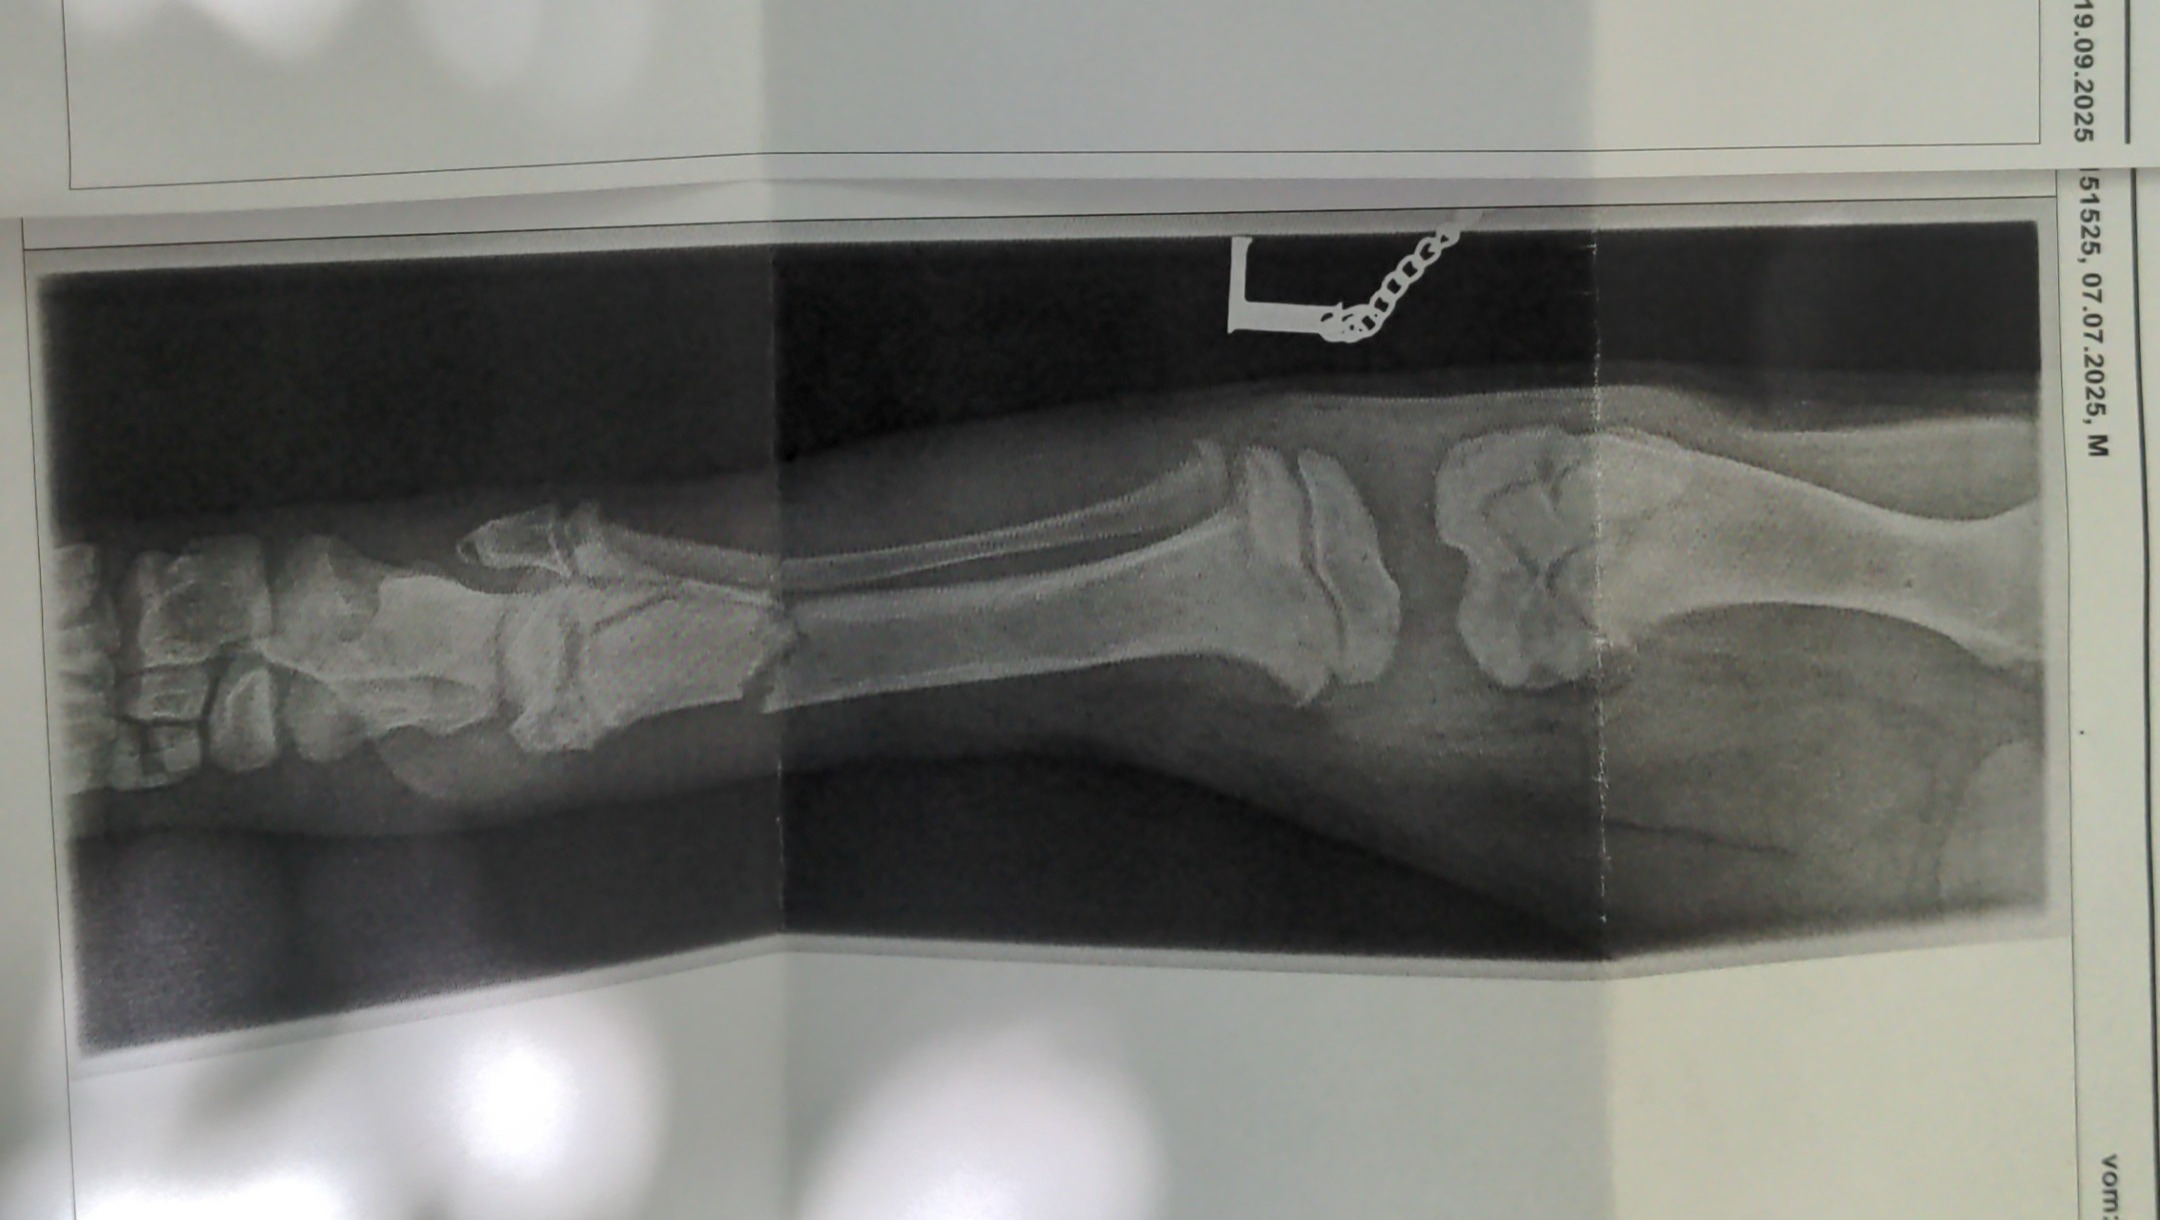

Mit der Besitzerin ging ich noch in der Schweiz am Tag nach dem Vorfall zur Untersuchung/Röntgen zum Tierarzt. Eine

Franktur an der Linke seite Hinten Tibia Fibula war die Diagnose. Da aus Fuchur ein Großer Hund wird, war eine Operation unausweichlich.

Am folge Tag (19. Sep.) wurde Fuchur in der Tierklinik Wiesloch operiert.

Die OP ist sehr gut verlaufen. Die Bruchstelle wurde mit einer Platte und Schrauben Fixiert.

Am Montag 06.10. wurden Kontroll-röntgenbilder erstellt und die Fäden gezogen. Der Bruch und die Op Wunde sehen sehr gut aus!!